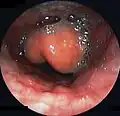

Diagnosis may be confirmed by direct inspection using a laryngoscope, although this may provoke airway spasm.[19] If epiglottitis is suspected, attempts to visualize the epiglottis using a tongue depressor are discouraged for this reason; therefore, diagnosis is made on basis of indirect fiberoptic laryngoscopy carried out in a controlled environment like an operating room.[19] An infected epiglottis appears swollen and is described as having a "cherry-red" appearance.[20] Imaging is rarely useful, and treatment should not be delayed for this test to be carried out.[19]

Swollen epiglottis in laryngoscopy